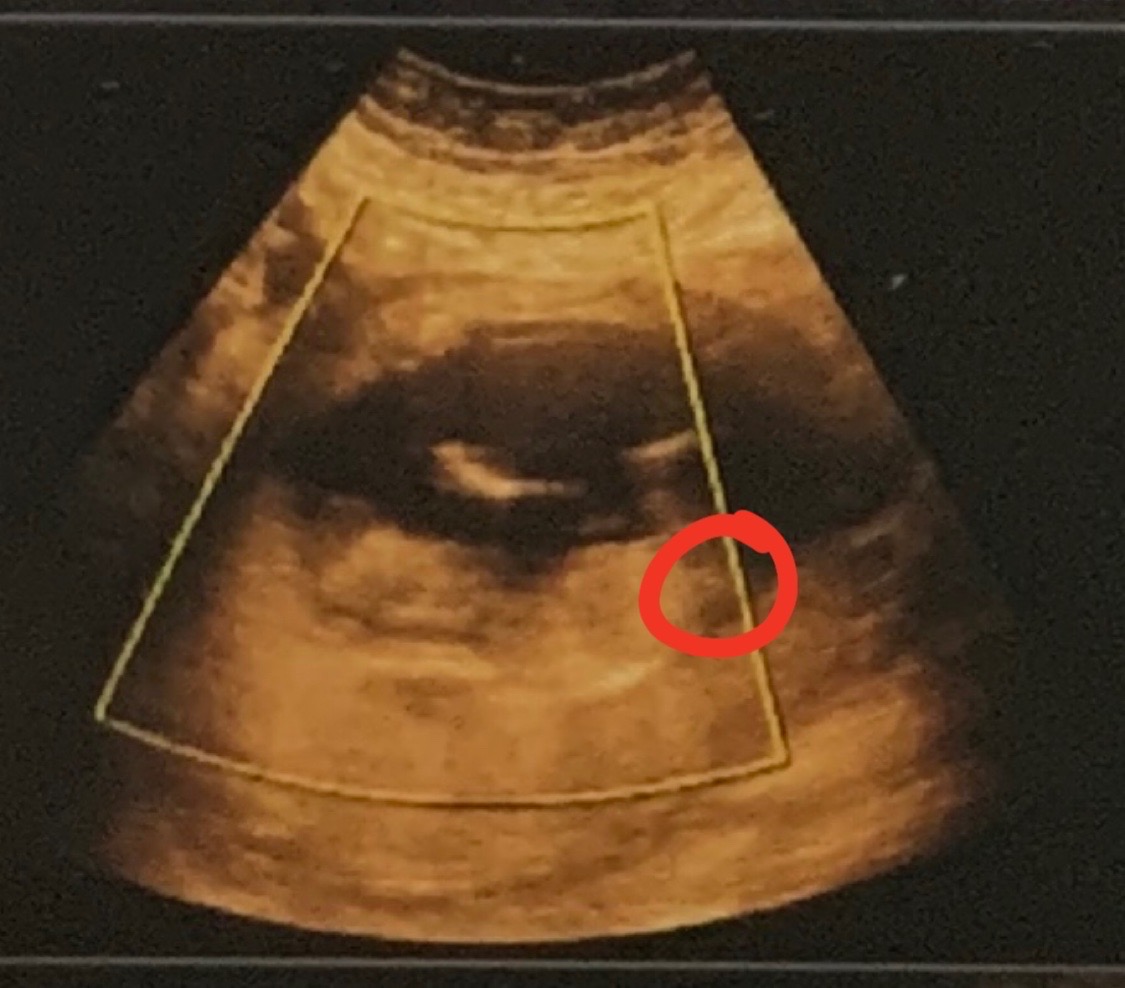

@sebinka123 na té poslední 2D fotce vidím holku 💃 na 13. týden si myslím, že by to mohla být spíš holka 🙂 4D fotky nejsou na upřesnění pohlaví dobré

@sebinka123 Já si myslím, že u Vás ten hrbolek je holčičí, na ten týden, kdy jste byla, by byl kluk víc nahoru a šikmý. Z té fotky, kde to vidím, miminko sice neleží úplně rovně, ale já si myslím, že to bude holka. My jsme vydrželi si neříct i u druhého, někdy to jsou nervy :D Ale při porodu to je pak zážitek 🙂 Já něco poznám z ultrazvuku, ale dokud to není oficiálně od dr., tak to beru jen jako můj tip ;) K tomu na tom ultrazvuku je to rychlé a vidíte jen chvilku něco, oproti fotkám, které máte v ruce a můžete zkoumat 🙂 Jinak já tohle těhu mám po tom 3. měsíci jiné, předtím mi bylo špatně jako s kluky, ale myslím, že to bylo teď méně a těhu nevolnosti už netrvají, kdežto s kluky ano a musela jsem furt jíst. Ale na tohle já moc nevěřím. My jsme třetí chtěli, i kdyby předtím byl páreček, ale teď by ta holka teda byla super :D

@sebinka123 Nevim... Nějak mám pocit i podle tvaru hlavičky, ze to bude spis holcicka 😂. Ale opravdu to berte jenom jako nějaké moje tušení/intuici. Oni ty snímky mohou často zkreslovat! Každopádně držím palce, ať to bude, co to bude 😘.

@sebinka123 ale fakt to není jisté, vyloženě pindoura tam nevidím, tady bych řekla jen tak na 65 % kluk ale pokud mi řeknete hodnotu hcg tak si budu jistější